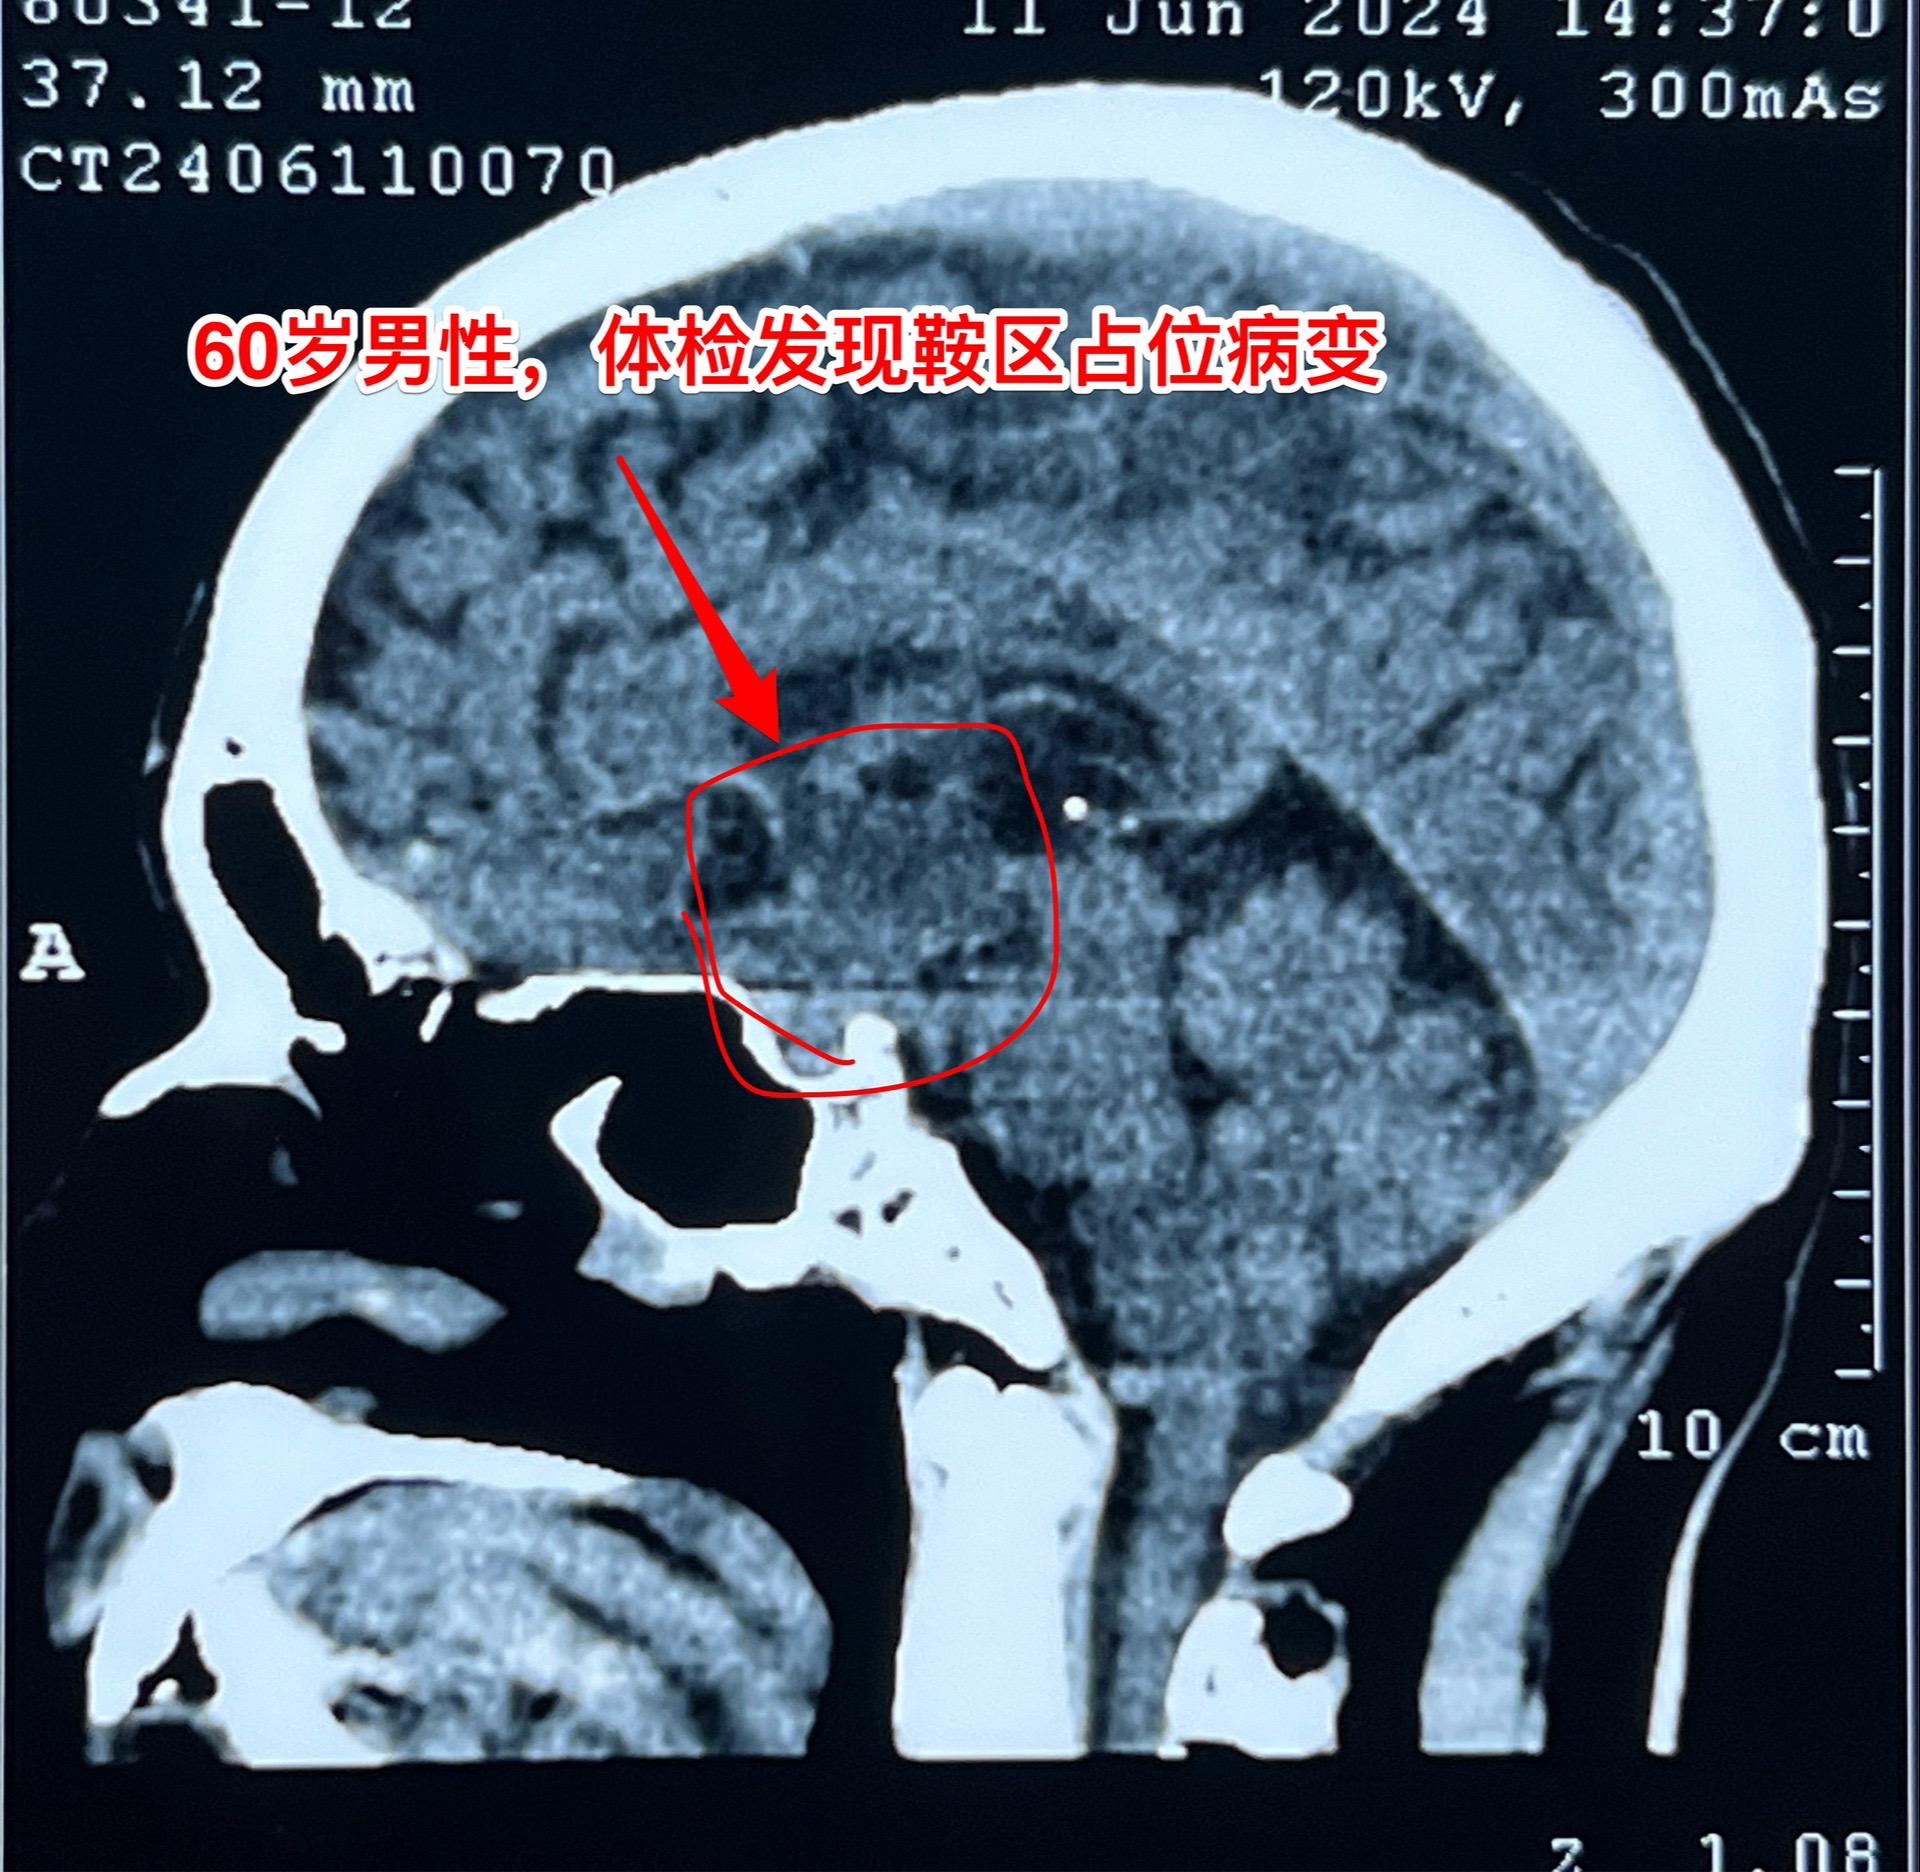

5月31日的颅咽管瘤手术。41岁山西男性,因思维糊涂、记忆力差发现鞍区肿瘤,为乳头型颅咽管瘤。 常规的经额底纵裂入路,将肿瘤完全切除。手术后病人的精神状态很好。 五月份的一共完成21台手术,其中20台为颅咽管瘤(今年一共80个颅咽管瘤手术),另一台为鞍区皮样囊肿! 在神经外科界,鞍区肿瘤的治疗是很有挑战性的![呲牙 2024-06-05 08:50